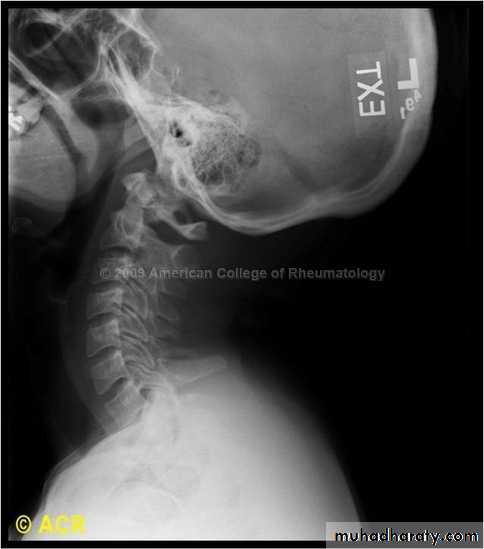

extension subluxation

frcature spine and peripheral nerve

A hyperextension

force may fracture the neural arch, especially of the atlas

Or fracture the dens (odontoid process) of the axis.

hyperextension may rupture the anterior longitudinal ligament and the

anulus fibrosus, forcing the vertebral bodies apart anteriorly (extension

subluxation) .

DIAGNOSISX RAY

Anterio posterior X ray radiograph.lateral radiographs with the head in flexion and extension may revealinstability that is not shown in the routine lateral film.